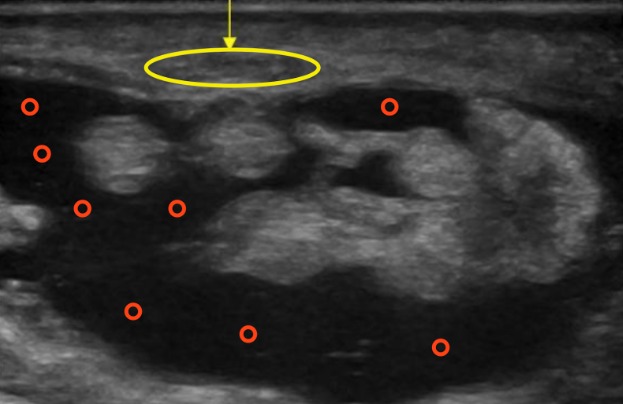

Como mencionamos anteriormente, la ecografía también facilita el diagnóstico diferencial al evaluar otras estructuras que podrían ser fuente de dolor, ya sea porque comprimen al nervio mediano o porque constituyen la causa primaria del dolor.

Por ejemplo, en la siguiente imagen, vemos un caso de tenosinovitis (el líquido anecoico lo hemos señalado con círculos rojos). Además se puede ver una compresión del nervio mediano (señalado en amarillo) debido a la ocupación del espacio.